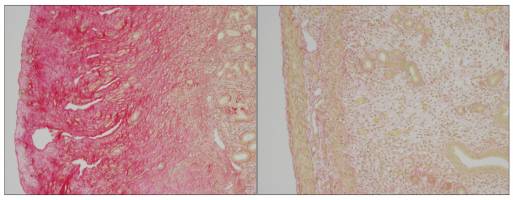

Sciences de la vie - Santé - 12.06.2017

Des scientifiques de l'EPFL ont identifié le mécanisme biologique derrière le Syndrome de la fibromatose hyaline, maladie défigurante, douloureuse et potentiellement mortelle.